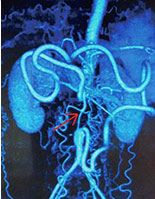

人工血管轉(zhuǎn)流術(shù)成功治療雙下肢動脈硬化閉塞癥

案例:我院人工血管轉(zhuǎn)流術(shù)治愈腹主動脈閉塞癥